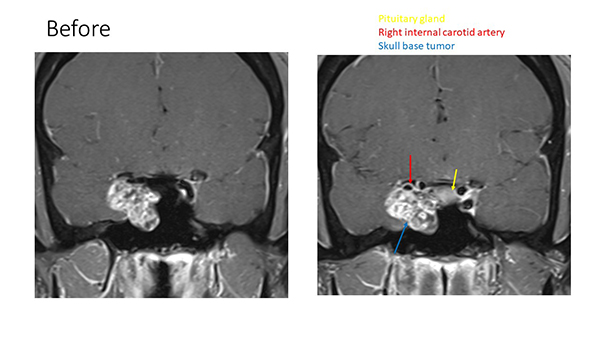

In this scan taken before surgery, doctors could identify the tumor in Pedro's head.

This MRI scan after Pedro's surgery shows the reconstructed nasal septal flap and relieved pressure on the carotid artery.